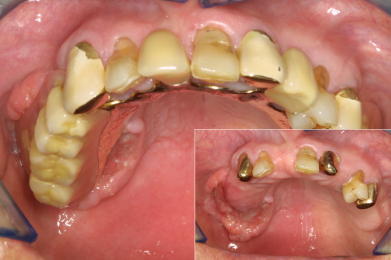

- Es fällt auf, dass ein oder mehrere Zähne stark wackeln oder eine Brücke lose ist

- Eine Krone oder Brücke ist aus dem Mund gefallen

- Prothesen werden nicht mehr getragen

- Prothese wird nicht regelmäßig herausgenommen

- Prothesen lösen sich immer wieder unkontrolliert beim Sprechen, häufiger fallen die Prothesen einfach aus dem Mund / Sprache ist undeutlich und Person spricht auffällig wenig

- Essen wird verweigert / Teilprothesen bzw. Totalprothesen vorhanden

- Feste, harte Kost wird verweigert / Gesicht bei fester Nahrung häufiger schmerzverzerrt